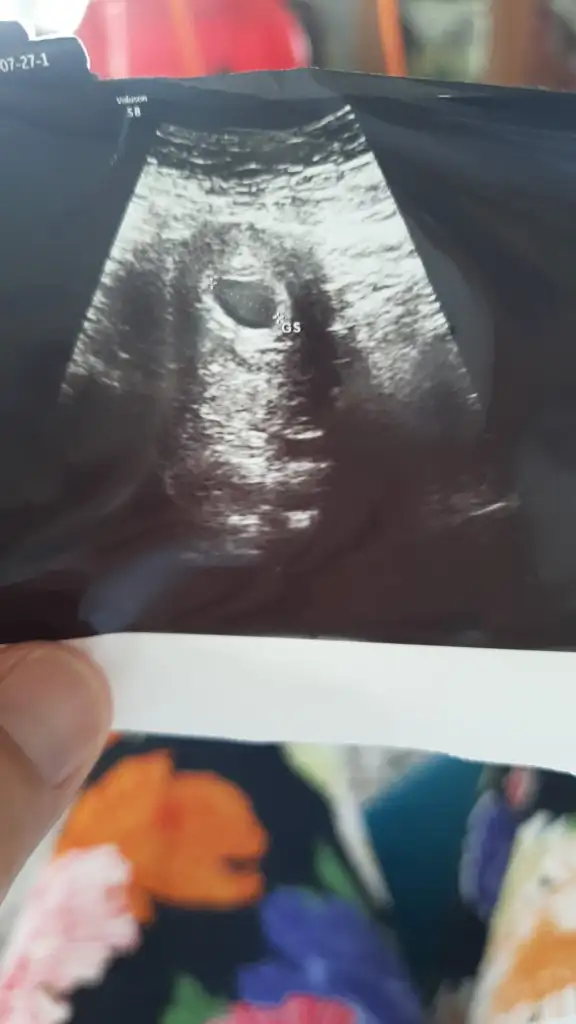

Valla canim bu durumlarda beklenmiyor var mı yok mu siniri bozuluyor insanin o yüzden gel diyorsa git rahatla ben bir hafta sonra gidicektim yarın gidiyorum kese var mı yoksa bu 20067 neyin nesi devlet de bu soruma cevao bulamadım özele gidiyorumCanım merhaba kese gözüktü ama henüz içinde bebeiş yokbebeğin oluşacağı yerde hazır herşey yolunda cumartesi gelirsen bebeği görürüz dedi ama ben haftaya cumartesi gitmeyi düşünüyorum kalp atışıda oluşması içim bakalım kısmet dünyada yiyecek rızkı varsa gelsin yavrum

Kese kaç cm burda ultrasonda yazarBende aynen öyle dedim doktora ama süreç gayet normal işliyor şu anda tedirgin olucak bi durum yok dedi ki benim bir düşüğüm olduğunu özellikle belirttim ama bu cumartesi gitsem sadece bebeği görücek varsa sonrasında gene kalp atışı için gitmem gerek kendimi de bu strese sokmak istemiyorum